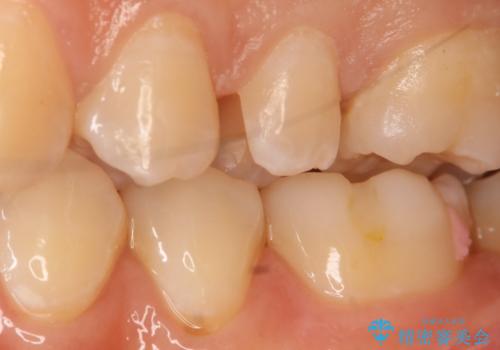

- 左上5番の虫歯治療を主訴に来院された患者様です。

セラミックでの治療を希望されたので形態・切削量を考慮しセラミックインレーでの治療を選択しました。

隣り合っている面(隣接面)は清掃がしづらく虫歯になりやすい場所です。

また、形態の再現が難しいのでインレーなどの補綴物での治療が第一選択となることが多いです。